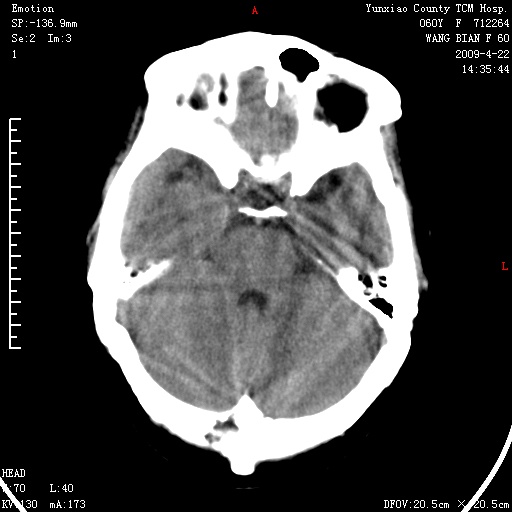

标题: CT19525:体检

1、头颅未见明显异常。

脑正常,肾有事,须强化,再定性.

1、头颅未见明显异常。2、左肾囊肿可能。建议增强

头颅未见明显异常。左肾囊肿。